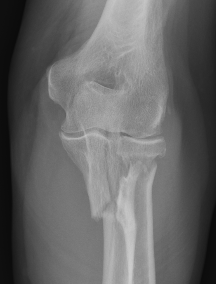

Definition

Elbow dislocation + olecranon fracture + radial head/neck fracture +/- coronoid fracture

Bado Type II most common in adults with posterior radial head dislocation

Bado type I Bado type II